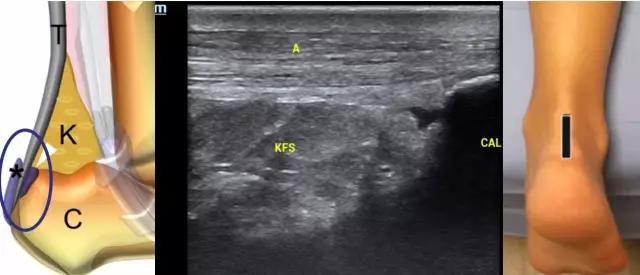

图3 正常跟腱长轴切面,SO 比目鱼肌,FHL 踇短屈肌,A 跟腱,KFSKagar脂肪垫,CAL 跟骨

图4 跟骨后滑囊 A 跟腱,C跟骨,K Kagar脂肪垫